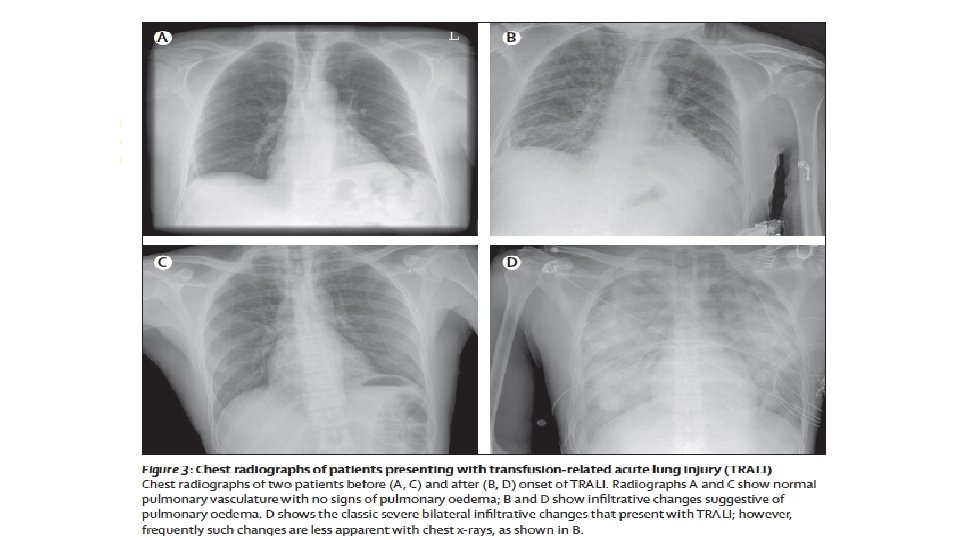

CRITERIOS En pacientes sin evidencia de lesión pulmonar aguda (ALI) antes de la transfusión, se diagnostica TRALI si hay un nuevo ALI y deben de cumplirse los cinco criterios: Ø Inicio agudo Ø Hipoxemia con: • Pa. O 2 ( presión parcial de oxígeno)/Fi. O 2 (fracción inspirada de oxígeno) menor o igual a 300 mm. Hg, Cociente que mide indirectamente la lesión pulmonar o • La saturación de Oxígeno es de <90% • Otras evidencias clínicas Ø Infiltrados bilaterales en la Rx de tórax Ø No hay evidencia de hipertensión auricular izquierda (sobrecarga circulatoria) Criterios revisados en 2017 Ø No hay relación temporal con un factor de riesgo para lesión pulmonar durante o dentro de las 6 horas posteriores al término de la transfusión 23

Como se presenta, TRALI? TRALI se define como la presencia de una nueva lesión pulmonar aguda, desarrollada dentro o durante las 6 horas posteriores a la transfusión sanguínea y no cuenta con relación temporal con los factores de riesgo para SDRA La patogénesis de TACO, TRALI y p. TRALI diferenciarlos clínicamente sigue siendo un desafío diagnóstico. 10 Se caracteriza por edema pulmonar e insuficiencia respiratoria, la cual se manifiesta por disnea, taquipnea e hipoxemia, taquicardia, fiebre, hipotermia e hipotensión 3. 3 Sofiane Tariket, Caroline Sut, Hind Hamzeh-Cognasse, Sandrine Laradi, Bruno Pozzetto, Olivier Garraud & Fabrice Cognasse (2016): Transfusion-Related Acute Lung Injury: Transfusion, Platelets and Biological Response Modifiers, Expert Review of Hematology.